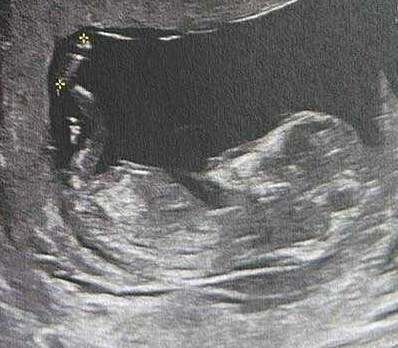

Hej dziewczyny! Czy któraś z Was z własnego doświadczenia potrafi mi podpowiedzieć czy to może być dziewczynka czy chłopiec?) 12+3Zobacz załącznik 1710846